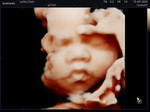

การจัดฟันในคุณแม่ตั้งครรภ์